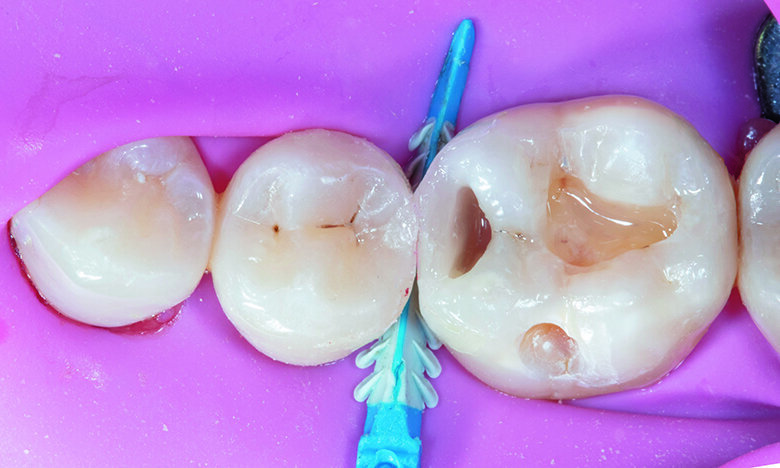

Prior to caries removal, proper quadrant isolation was done with placement of rubber dam and pre-wedging with Garrison small FXBL wedge.

Tip: Pre-wedging creates momentary tooth separation to help achieve a more accurate proximal seal with ideal contact after placement of the final restoration and the teeth return to their original position. In addition, it helps to protect the rubber dam when removing the caries in the cervical area.

Caries removal was completed with a blue stripped high speed small round bur followed by slow speed round carbide bur. Caries detection dye was applied to ensure complete removal of active decay. Old composite was removed from occlusal and buccal pit area of tooth #46. For tooth #45, decay was initially removed without touching the occlusal surface, however as the marginal ridge area was left with very thin structure, the proximal box was later extended to the occlusal surface (C-shaped preparation) to avoid excessive stress that could lead to restoration failure (Fig. 2).

Fig. 2. Pre-wedging with removal of active decay on teeth #45, 46.